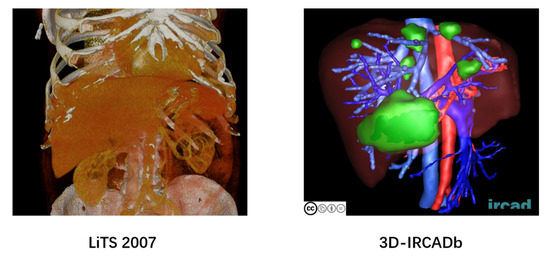

3.1. Experimental Preparation and Protocols